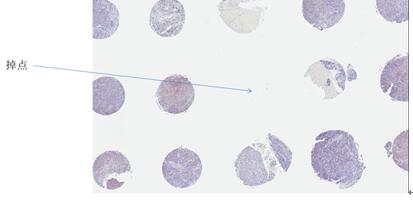

问题1:使用40-58°C加热时间过长或温度高过58度,就会产生肉柱倒塌、悬浮、肉柱无法有效融蜡的问题,导致最终切片时的折点、掉点。

- 预制受体蜡块没有内部气泡产生,规避折点、掉点

- 切片后成果,完整与整齐的组织芯片利于后续镜下观察和扫描